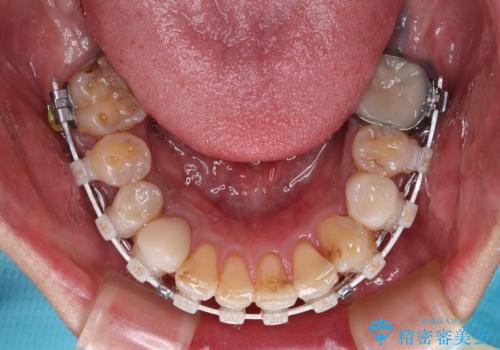

抜歯が必要な歯は事前に抜歯をし、その後ワイヤー装置にて歯列矯正を行い、途中でインプラントを埋入し、オールセラミッククラウンにて補綴治療を行うこととしました。

矯正治療にやや時間がかかりましたが、歯列はきれいに整い、気になっていたむし歯や銀歯は自然な色合いに仕上がりました。

- 治療中は違和感や痛みが起こることがあります

- 症状により、抜歯が必要な場合があります

- 治療中は歯磨きがしにくくなるため、虫歯や歯周病になりやすくなります